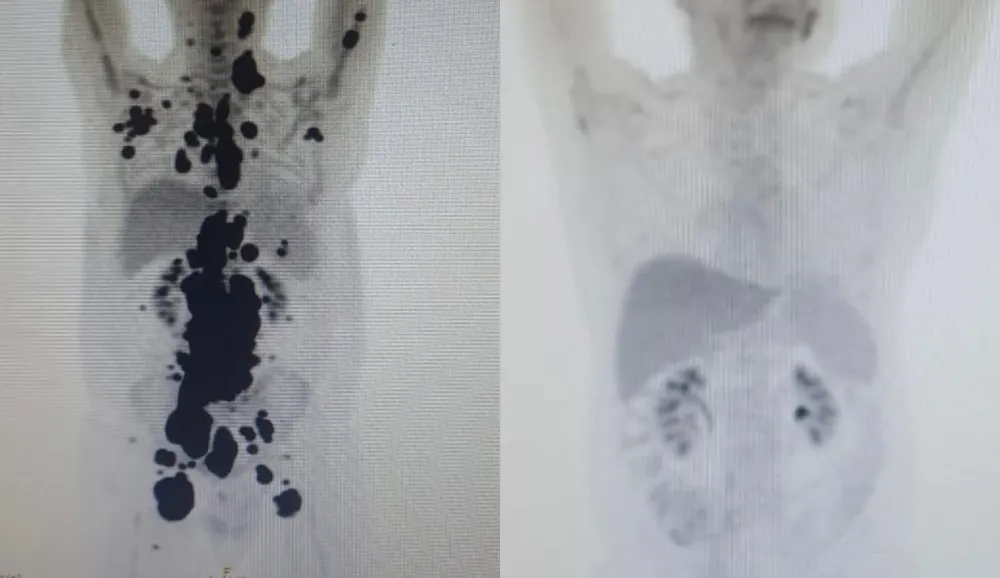

Uma tomografia feita por Paulo antes e depois do tratamento, mostram como o uso da CAR-T Cell fez toda diferença no processo de remissão que o homem sofreu.

“Foi uma resposta muito rápida e com tanto tumor. Fiquei muito surpreso de ver a resposta, porque a gente tem que esperar pelo menos um mês depois da infusão da celular”, disse Vanderson Rocha, coordenador nacional de terapia celular da rede D’Or e professor da USP.

“Quando a gente viu, todo mundo vibrou. Coloquei no grupo de professores titulares da USP e todo mundo ficou impressionado ao ver a resposta que ele teve”, disse Vanderson.